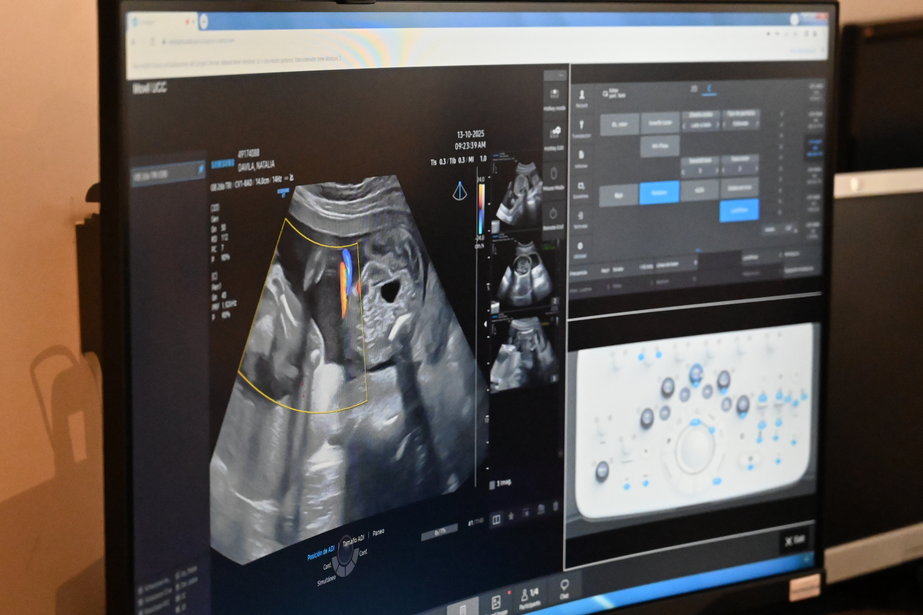

La médica ginecoobstetra Ana Bianchi es la directora del Departamento de Medicina Fetal del Pereira Rossell, que lleva adelante esta labor mediante el uso de una tecnología de avanzada, denominada Eco Stream, que permite realizar ecografías a distancia.

Bianchi contó cómo a partir de un equipamiento especial provisto de un software que incorpora inteligencia artificial, su equipo puede realizar ecografías desde el Pereira Rossell, tal como si estuviera a centímetros de la paciente. "Nosotras controlamos el 100% del equipo, hacemos los diagnósticos sin necesitar que haya un técnico del otro lado", explicó.

Actualmente, este proyecto piloto abarca tres centros: Canelones, Artigas, y un móvil que permite mejorar el acceso de las mujeres embarazadas a los controles obstétricos en tiempo y forma, directamente con el equipo técnico especializado del Pereira Rossell, sin necesidad de traslados hasta la capital por exámenes que muchas veces se resuelven en unos pocos minutos. "La idea es irlo ampliando a otras localidades", afirmó Bianchi.